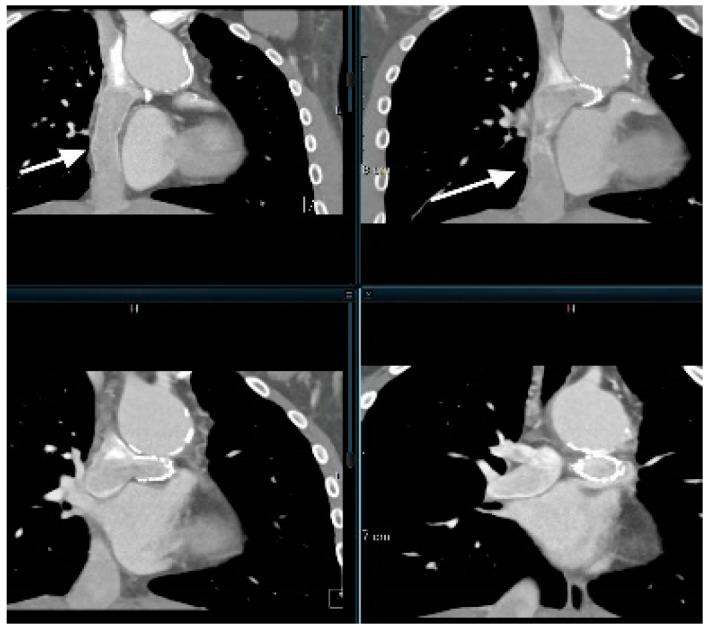

多模态成像与心脏科-放射科先天性心脏病接口入门

A Primer on Multimodal Imaging and Cardiology-Radiology Congenital Heart Interface.

Pediatric cardiology imaging laboratories in the present day have several modalities for imaging of congenital and acquired cardiovascular disease. These modalities include echocardiography, cardiovascular magnetic resonance imaging, cardiac computed tomography and nuclear imaging. The utility and limitations of multimodal imaging is described herein along with a framework for establishing a cardiology-radiology interface.

当今的儿科心脏病学影像实验室拥有多种用于先天性和后天性心血管疾病成像的模式。这些模式包括超声心动图、心血管磁共振成像、心脏计算机断层扫描和核成像。本文描述了多模态成像的效用和局限性,并给出了一个建立心脏病学与放射学接口的框架。